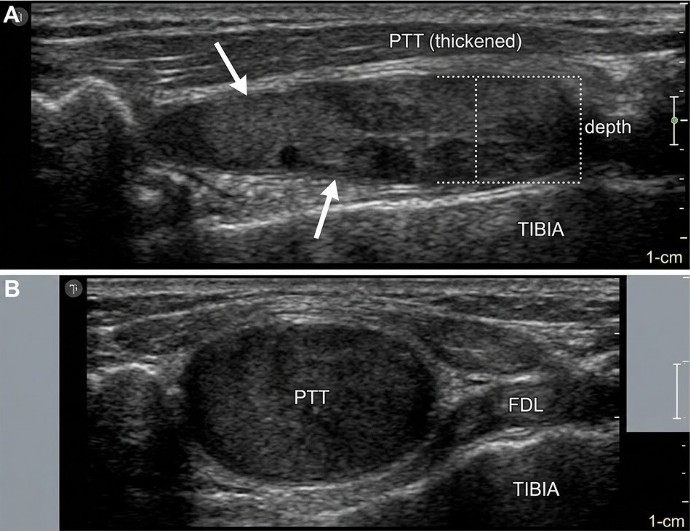

En el eje largo (Imagen A), el cambio es evidente: el tendón presenta un engrosamiento fusiforme marcado (PTT thickened). Se ha perdido el patrón fibrilar brillante; ahora el tejido es más oscuro (hipoecoico) debido a la degeneración del colágeno, mostrando una estructura desorganizada que confirma una tendinopatía crónica sin signos de rotura.

En el eje corto (Imagen B), la clave es el aumento de volumen. El tendón tibial posterior (PTT) se ve desproporcionadamente grande y redondeado en comparación con el tendón flexor largo de los dedos (FDL). Esta pérdida de la forma compacta y su tono oscuro son los hallazgos clásicos de un proceso degenerativo.